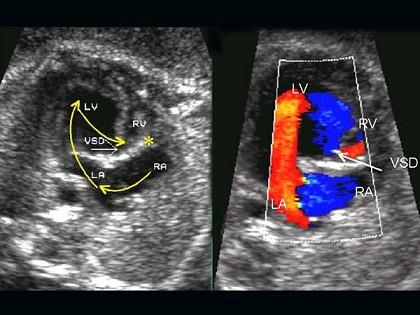

问题 女孩,9岁。平时乏力,活动后气促,胸骨左缘第34肋间闻及ⅢⅣ级全收缩期杂音,经超声心动图检查,如图,确诊为先心病,室间隔缺损。下列哪项不是其常见并发症 ( )

选项 A、感染性心内膜炎 B、脑血栓形成 C、支气管肺炎 D、充血性心力衰竭 E、肺水肿

答案 B